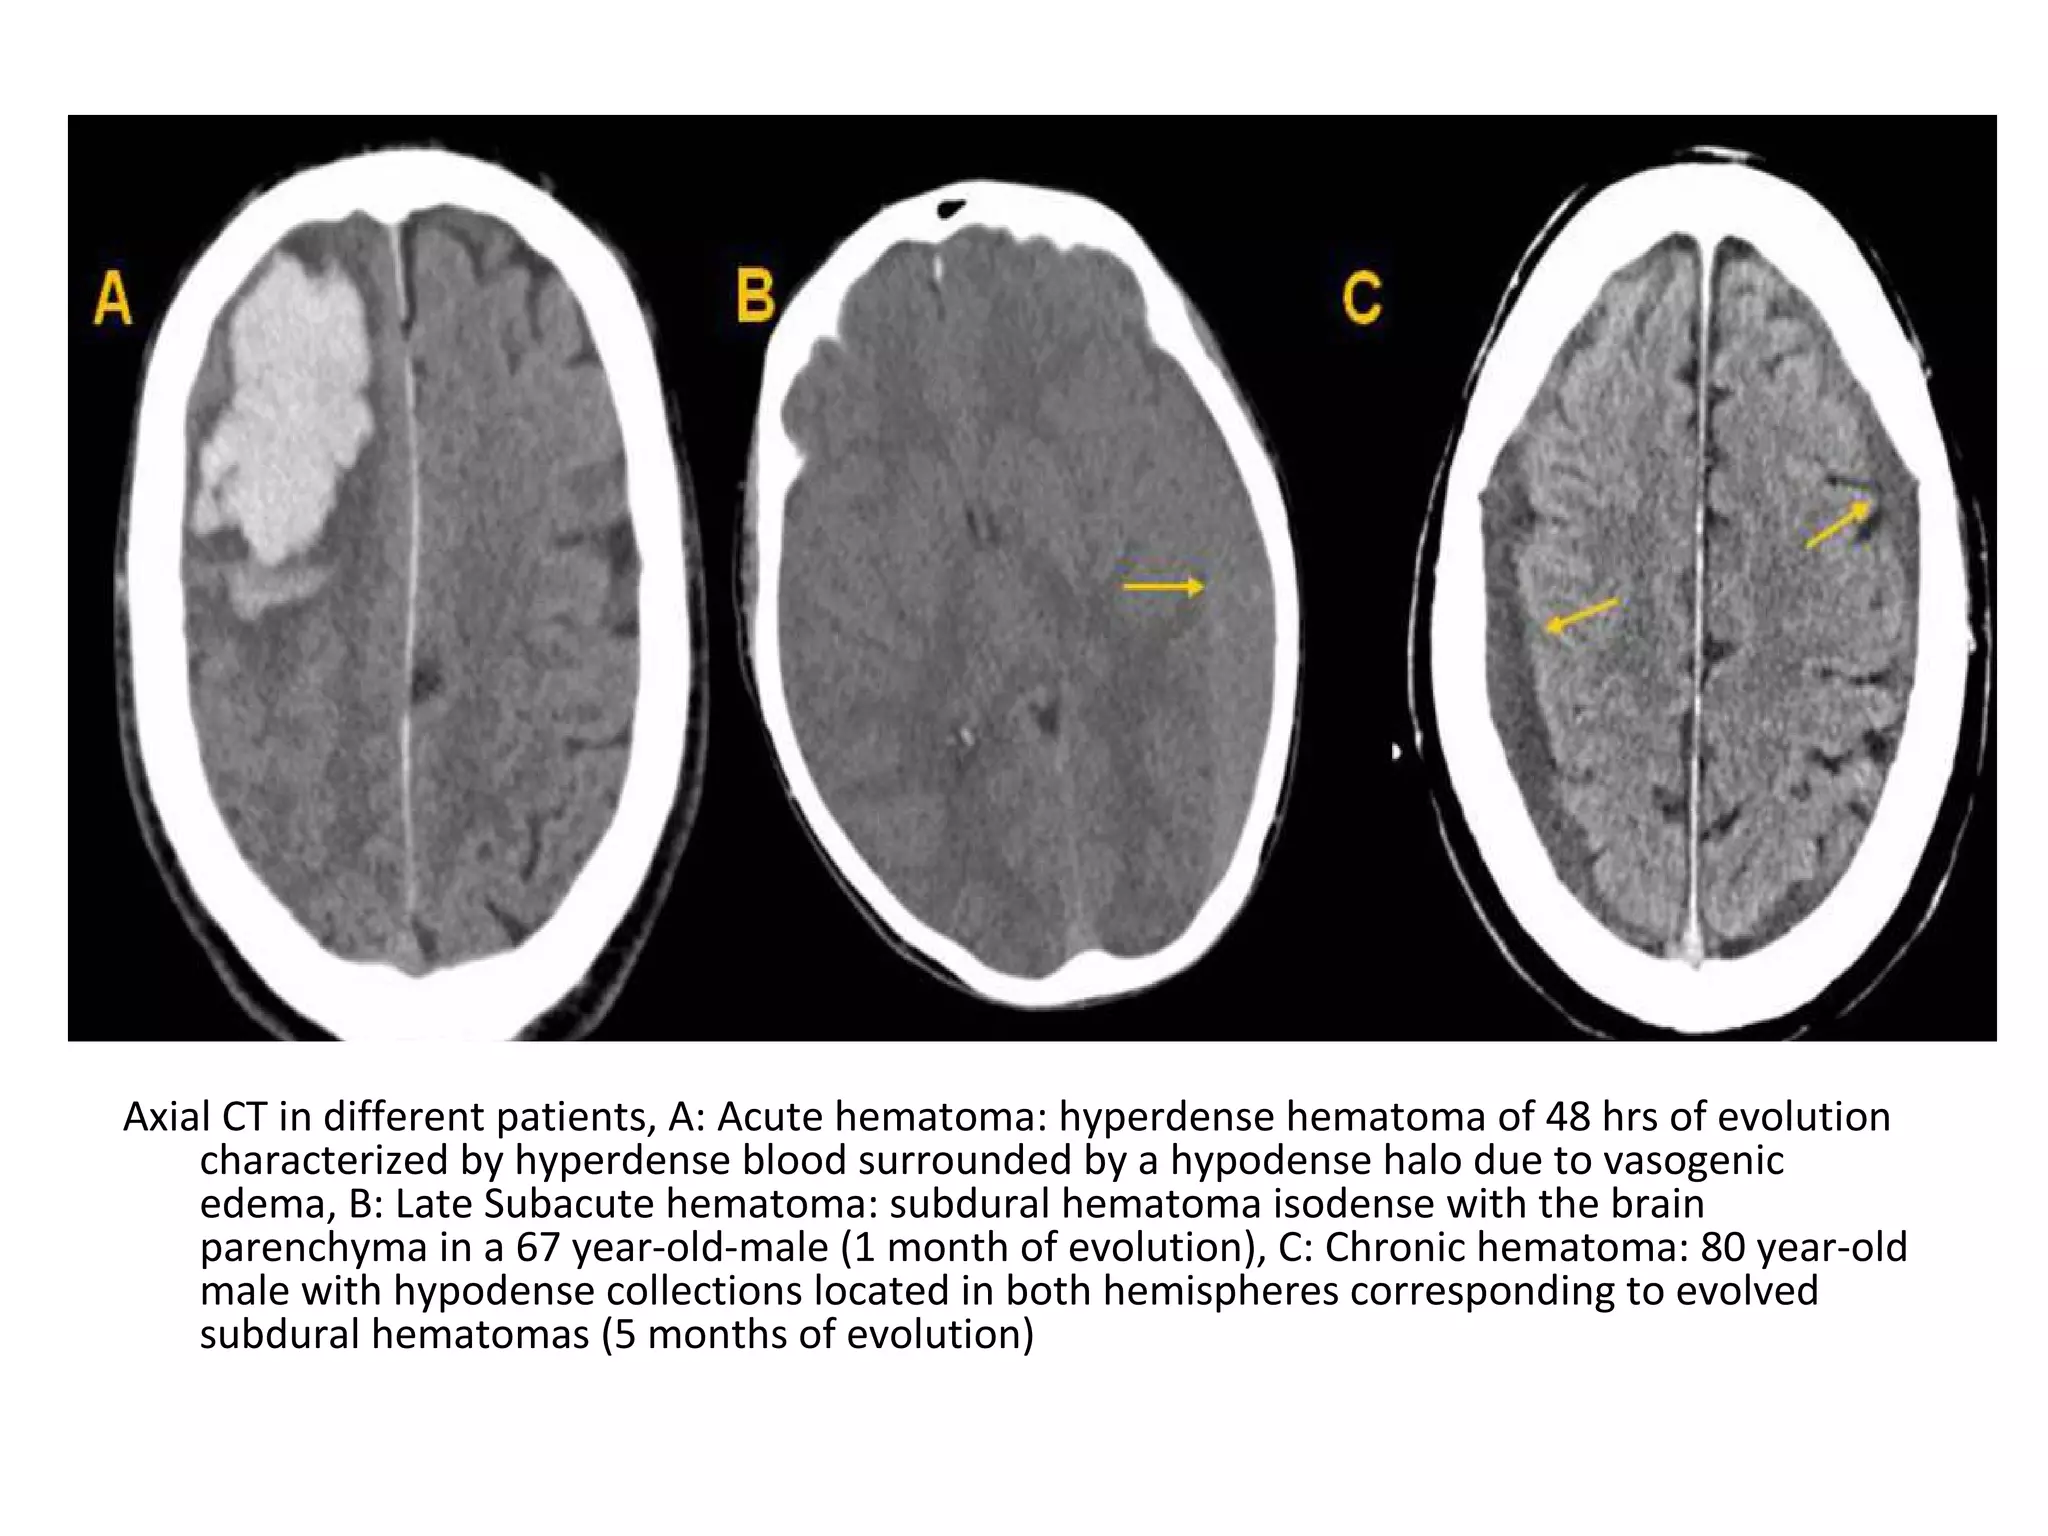

b) Radiological Findings :

-Acute thrombus is hyperdense on precontrast CT

and expands the occluded sinus / vein (Dense

clot sign)

- Cord sign : is defined as a homogeneous ,

hyperattenuated appearance of thrombosed

venous sinuses , the hyperattenuated

appearance of the affected veins often being

named (the attenuated vein sign)

Direct visualization of a clot in the cerebral veins on a non enhanced

CT scan is known as the dense clot sign

Dense clot sign in a thrombosed cortical vein

CT without contrast : Cord Sign , in the SSS (dotted arrow)

and the RTS (arrows)

Attenuated vein sign in both ICVs (thin arrows), in the SS (crossed arrow)

Hemorrhagic infarction in the temporal lobe (red arrow) , notice the dense

transverse sinus due to thrombosis (blue arrows)